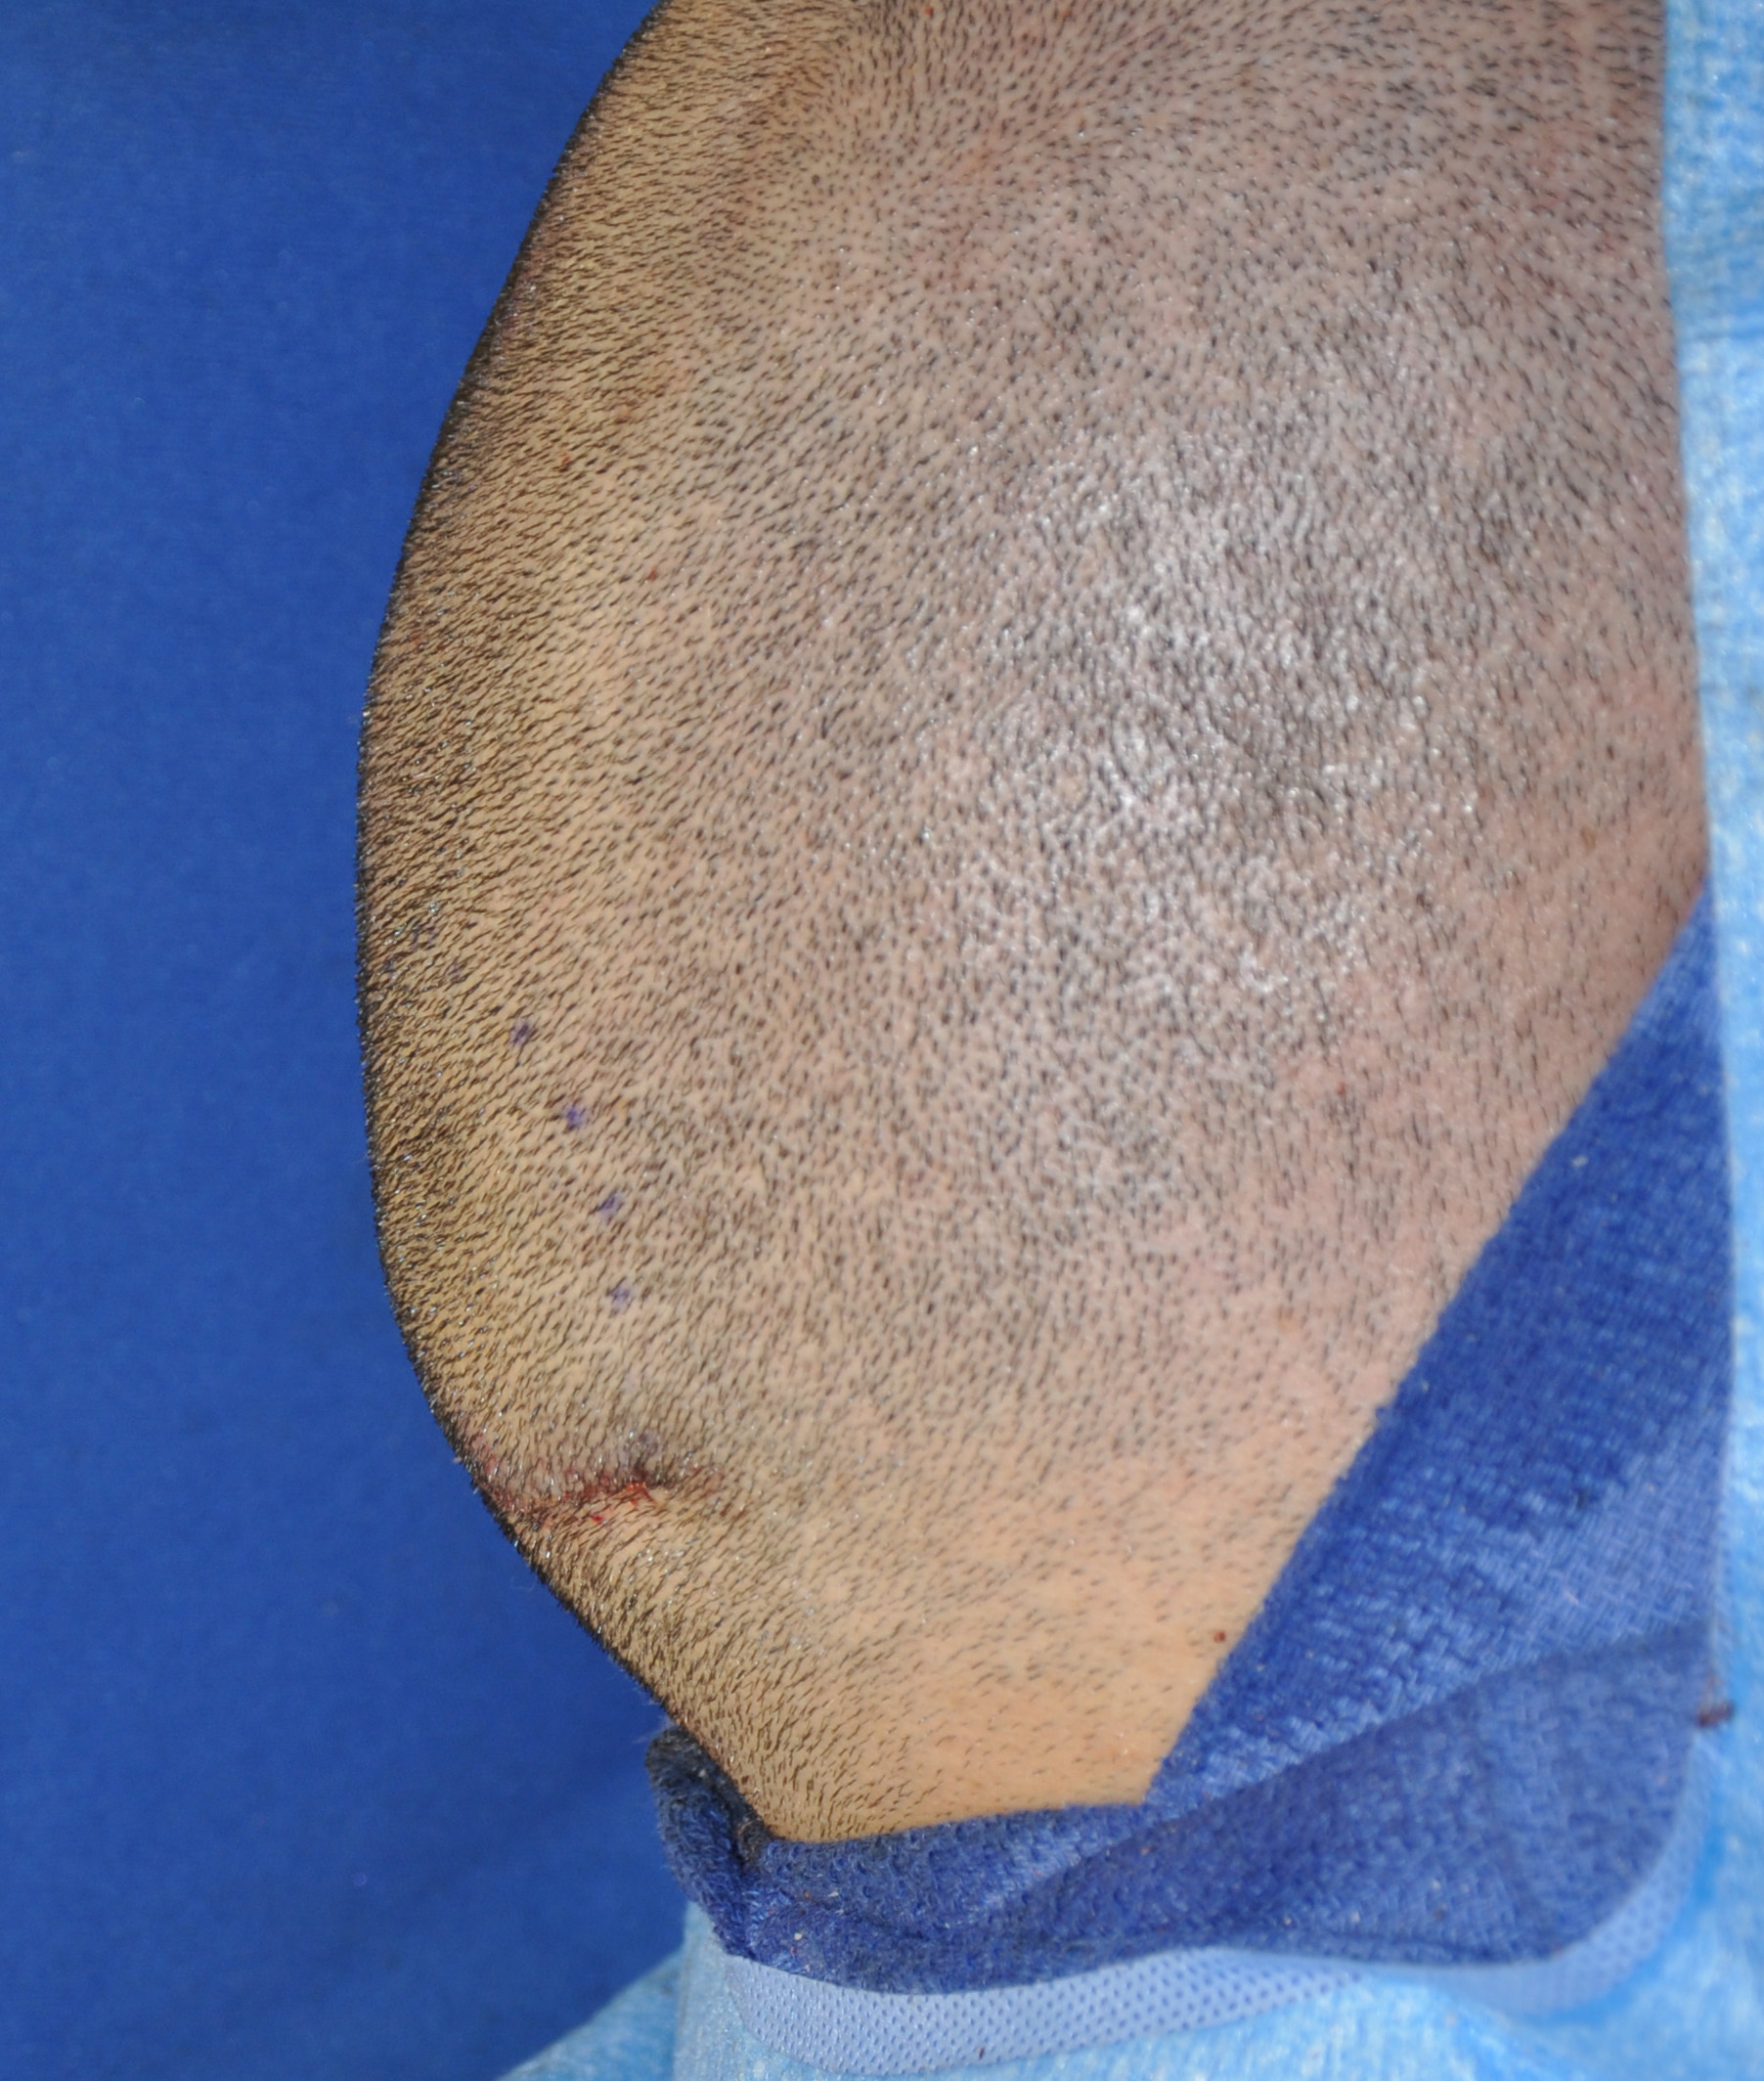

57

Scalp avulsion due to traumatic injury which left a large patch of non-hair bearing scalp.

Hair bearing scalp reconstruction using a first stage tissue expanders and second stage scalp scar removal.

Scalp avulsion due to traumatic injury which left a large patch of non-hair bearing scalp.

Hair bearing scalp reconstruction using a first stage tissue expanders and second stage scalp scar removal.